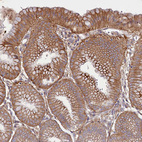

Immunohistochemical staining of human stomach shows positivity in glandular cells.